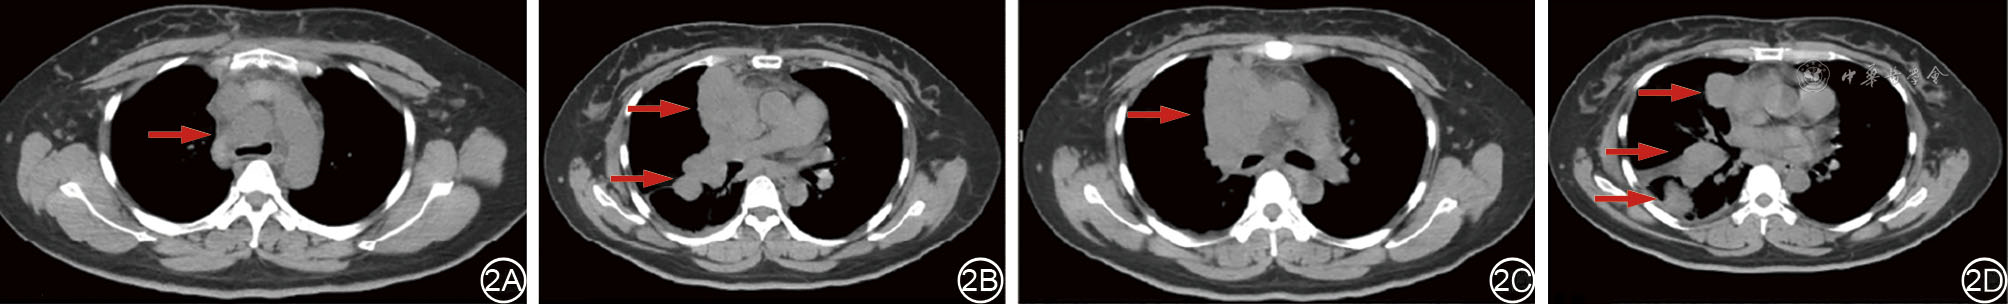

We present a case of a 40-year-old female patient with midline carcinoma, who was admitted for chest pain and cough and diagnosed with concurrent mediastinal and pulmonary metastases. Single-agent chemotherapy proved ineffective and her clinical symptoms aggravated, accompanied by tracheal and superior vena cava compression. Following multidisciplinary consultation, CT-guided 125Ⅰ seed implantation was initially performed. Local tumors regressed postoperatively while partial pulmonary metastatic lesions progressed, prompting seed reimplantation combined with bronchial arterial chemoembolization, followed by concurrent anlotinib targeted therapy and sintilimab immunotherapy. After six months of comprehensive treatment, the thoracic tumors resolved, lymph nodes shrank, radiological evaluation indicated partial response, and the patient's clinical symptoms were significantly relieved. This case demonstrates that the integrated regimen of interventional local therapy plus targeted and immunotherapy offers a viable therapeutic approach for inoperable midline carcinoma patients with refractory conventional chemotherapy, enabling rapid symptom relief and improved treatment efficacy.